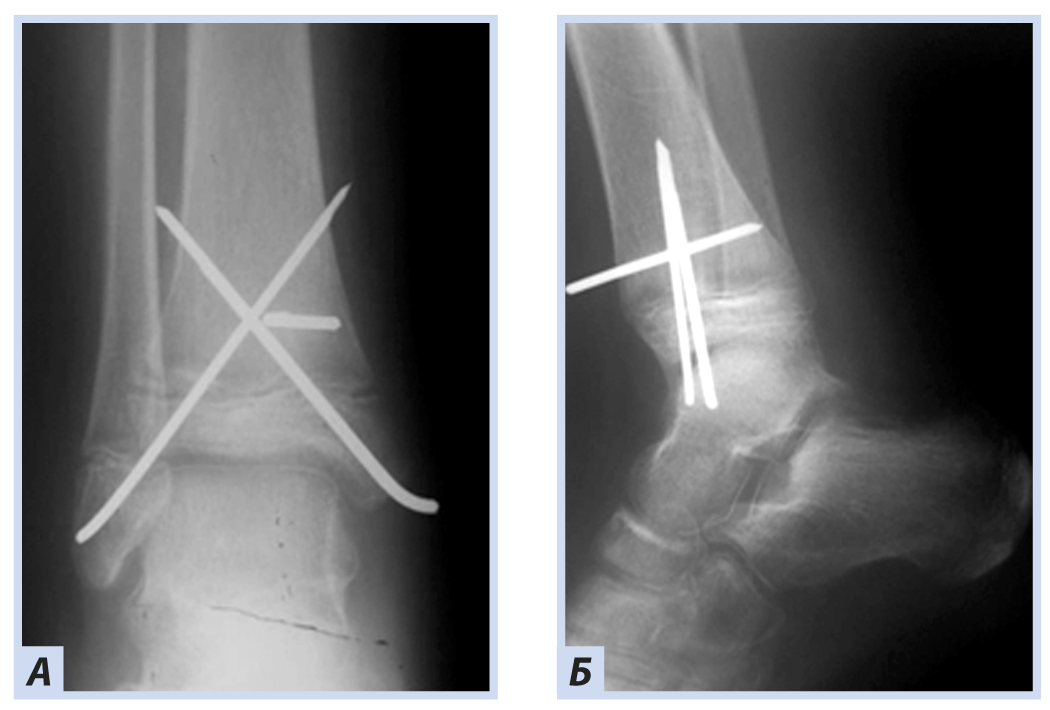

Клиническое наблюдение 3

Мальчик, 16 лет, диагноз «Закрытый перелом обеих лодыжек правого голеностопного сустава с подвывихом стопы кнаружи. Супинационно-эверсионный механизм травмы». Травма получена в результате падения на льду. По данным ультразвуковой диагностики был диагностирован частичный разрыв передней порции дистального межберцового синдесмоза. Выполнен остеосинтез внутренней лодыжки спицами, дистальный межберцовый синдесмоз фиксирован синдесмозной системой (Arthrex Tightrope Ankle), перелом латеральной лодыжки фиксирован 1/3 трубчатой пластиной. Внешняя иммобилизация осуществлена гипсовой лонгетой. Контрольная рентгенография и исследование микроциркуляции в области перелома методом лазерной допплеровской флоуметрии выполнены через 8 нед. после операции. На рентгенограммах имеются признаки зажившего перелома, по данным флоуметрии наблюдается активация капилляризации тканей и нутритивного кровотока в условиях регенераторного процесса. Спицы удалены через 8 нед., конфигурация сустава восстановлена полностью (рис. 10–13).

Рис. 12. Тот же пациент. Рентгенограммы дистального отдела костей правой голени. Остеосинтез малоберцовой кости пластиной, остеосинтез внутренней лодыжки спицами, фиксация синдесмоза системой Arthrex Tightrope Ankle: А — прямая проекция; Б — боковая проекция.

Рис. 13. Тот же пациент. Рентгенограммы дистального отдела костей правой голени через 8 нед. Консолидация костных отломков: А — прямая проекция; Б — боковая проекция.